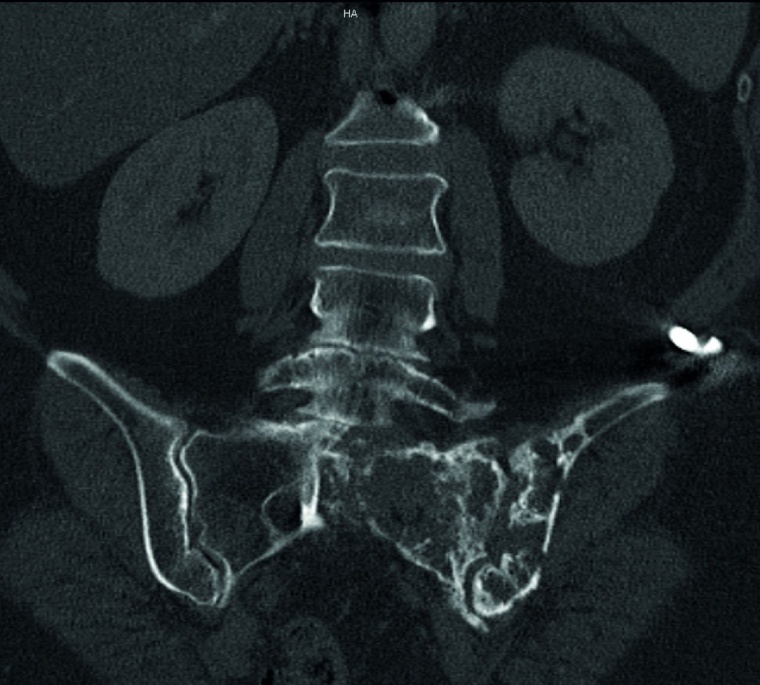

Sakrummetastasen: Stabilitätsgefährdende Metastasen am Sakrum (Abb. 3a) und am hinteren Beckenring werden zumeist mit einer mono- oder bilateralen vertebropelvinen Abstützung versorgt (Abb. 3b). Insbesondere das Os sacrum kann so aus der lasttragenden Kette herausgenommen werden. Vor allem bei Mammakarzinommetastasen kann mit der nachfolgenden Radiatio häufig eine so stabile Rekalzifikation erzielt werden (Abb. 3c), dass mitunter bei Beschwerden über dem Fixateur besonders bei schlanken Patienten eine Metallentfernung erwogen werden kann. Sollte das dorsale Os ileum mit betroffen sein (Abb. 4a) kann bei entsprechenden anatomischen Voraussetzung (Abb. 4b) auch weiter ventral auf den Beckenkamm abgestützt werden (Abb. 4c).